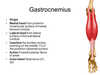

gastrocnemius

soleus

- under gastrocnemius